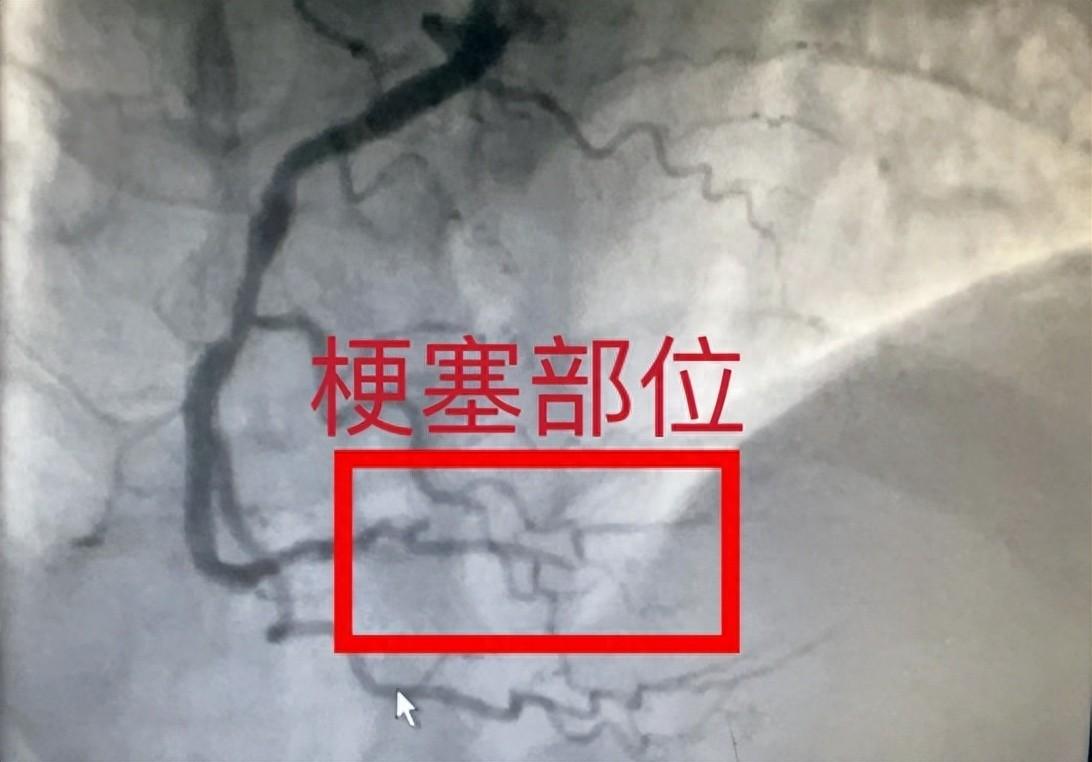

湖南省第二人民医院(湖南省脑科医院)心血管内科副主任医师李贺介入团队对汤先生连夜展开抢救,经过急诊冠脉造影检查,汤先生右冠状动脉中段狭窄70%,远端闭塞,情况十分危急,由于患者拒绝行支架植入手术,经和家属沟通商量后在远端闭塞部位给予了药物球囊扩张治疗。经过积极抢救,汤先生胸闷心悸等症状明显好转。